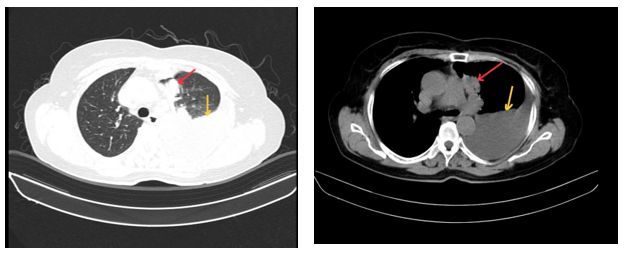

- Cắt lớp vi tính ngực (Bệnh viện Bạch Mai): Phổi trái: Phân thùy S3 có khối tỷ trọng tổ chức kích thước 24x15mm, ngấm thuốc sau tiêm bờ không đều xâm lấn vào màng phổi trung thất, động mạch, tĩnh mạch phổi trái gây huyết khối bán phần. Xẹp thụ động thùy dưới. Màng phổi trái: có nốt ngấm thuốc đường kính 8mm. Dịch khoang màng phổi trái dày 60mm gây xẹp thụ động thùy dưới. Hạch trung thất nhóm V, nhóm II, IV bên phải và carina lớn nhất kích thước 23x12mm. Hình ảnh tổn thương tiêu xương đòn trái.

Hình 1: Hình ảnh cắt lớp vi tính ngực lúc mới nhập viện: Khối tổn thương thùy trên phổi trái, tỷ trọng tổ chức, bờ không đều, ngấm thuốc không đồng nhất, xâm lấn màng phổi trung thất (mũi tên màu đỏ). Tràn dịch màng phổi trái lượng nhiều gây xẹp phổi thụ động thùy dưới (mũi tên màu vàng).